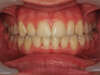

L'encombrement chez l'adolescent

Manque de place :

(encombrement - dysharmonie dento-maxillaire)